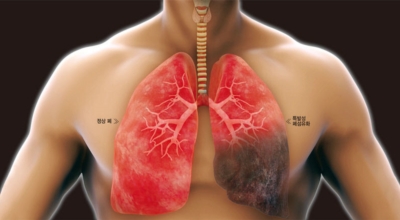

5. 긴 시간의 흡연은 기도의 보호 메커니즘을 훼손시켜 기관, 기관지, 폐 간질 및 폐에 훼손을 주어 폐 기능의 건강에 영향을 미쳐요.

인체가 순조롭게 기능을 발휘하려면 폐 건강이 필수다. 폐는 인체가 효율적으로 움직이는 데 있어 바퀴 안에 있는 톱니 같은 역할을 하기 때문이예요. 산소를 제공하는 폐 기능이 감소하게되면 폐렴이나, 만성 폐쇄성 폐질환(COPD), 천식 등 정도가 심한 호흡기 질환 발생 위험이 증가해요. 이런 질병들은 폐를 공격해 숨쉬기 힘들게 만들어요.